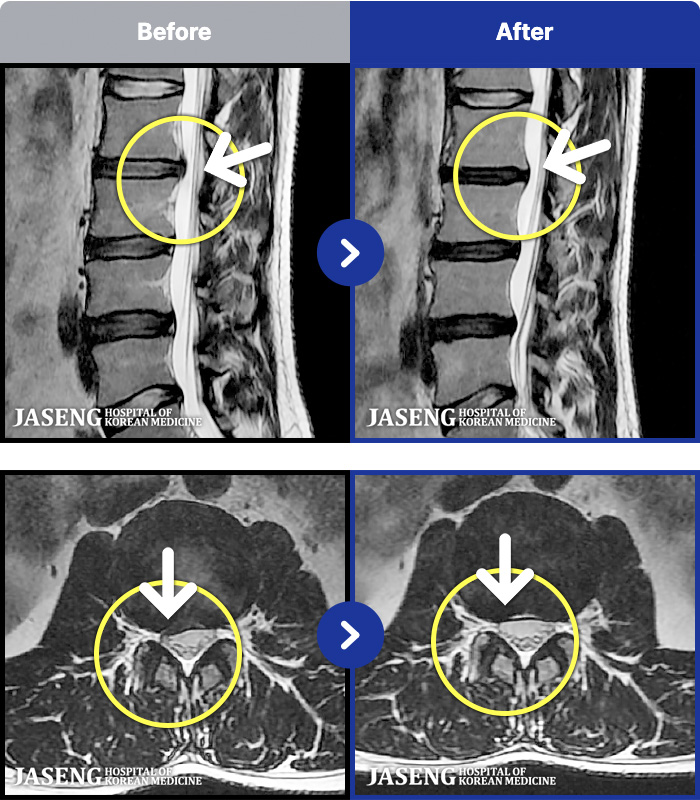

MRI ġ

MRI ũ ʸ Ȯϼ.

[_㸮ũ] 㸮 Ұ. ٸ , ȭŸ Ÿ

No.46

ȸ 576

2024.12.24